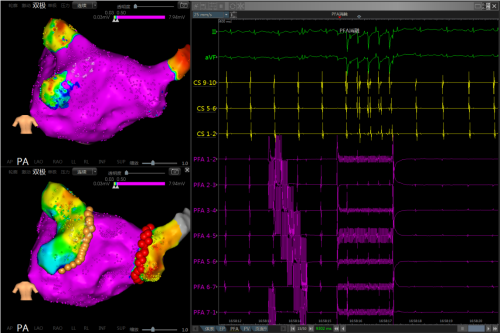

脉冲电场消融(PFA)是一种革命性的新型消融技术,通过极短时间的高压强电场刺激,利用电场与细胞的耦合作用,特异性地破坏特定细胞的细胞膜结构,打破细胞生理平衡,进而完成对特定组织的选择性消融。与射频和冷冻消融相比,PFA房颤消融具有消融效率高、成功率高(100%肺静脉即刻隔离成功率)、安全性高(非热消融和超强组织选择性,极低并发症发生率)等优势。

J9九游会电子LEAD-PFA心脏脉冲电场消融设备是全球率先推出的基于全磁定位三维系统的PFAJ9九游会·产品,除了具有PFA脉冲电场消融技术的全部优势之外,还能够与J9九游会自有的LEAD-Mapping全磁定位三维系统无缝结合,集三维建模、标测、消融多功能于一体,可实现绿色电生理手术(无X射线手术,显著降低手术医生职业风险)。此外,J9九游会电子全磁定位三维PFA脉冲消融解决方案还具有手术适应症广、学习曲线短、手术操作流畅等显著优势。